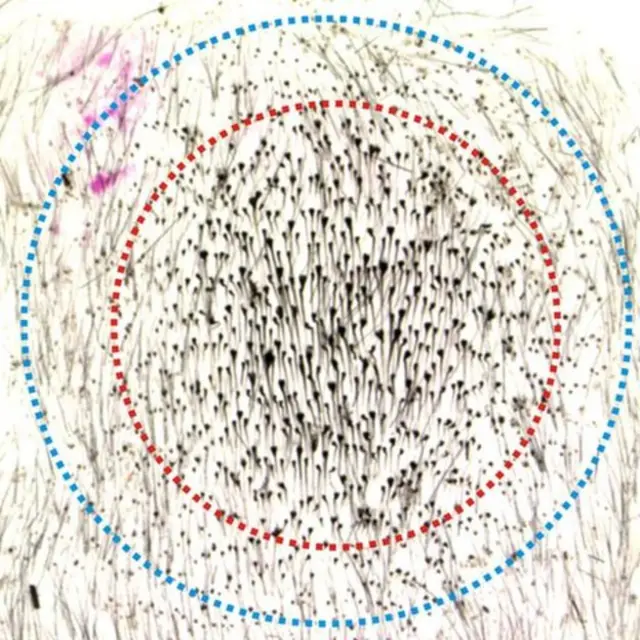

В ряде экспериментов исследователи выдернули у подопытных мышей 200 волосяных фолликул на круговом участке кожи. При редком выдергивании отдельных волосинок на участке диаметром 6 мм никакой регенерации не происходило.

Однако если удалялось 200 волосин на участке диаметром 5 мм, это приводило к появлению 1300 новых волосинок.

Но при более плотном удалении волос – того же количества, но на участке меньшего диаметра, в 4 мм, – появлялось 780 новых волос.